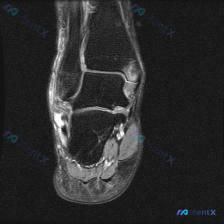

这是一份单张踝关节MRI T2序列轴位图像,临床疑问是观察到「软组织积液」,需要解读。

- 骨骼结构:可见胫腓骨远端截面,骨皮质轮廓清晰,骨髓信号没有异常高信号,排除明显骨挫伤、骨髓水肿

- 前侧软组织:胫骨前肌腱、踇长伸肌腱、趾长伸肌腱走行正常,没有异常增粗或信号改变

- 内侧(胫骨后方):胫骨后肌腱、趾长屈肌腱、踇长屈肌腱走行清晰,形态完整,没有明显腱鞘积液

- 外侧(腓骨后方):腓骨长短肌腱走行位置正常,信号均匀,没有撕裂或腱鞘积液

- 后侧:跟腱形态信号正常,低信号条带状,边缘光滑连续,周围脂肪间隙清晰,排除跟腱炎、跟腱周围炎

基于这张单层图像来看:所有主要肌腱都呈现正常低信号,没有明确的信号增高或形态异常,也没有看到明确的腱鞘积液或软组织水肿;胫腓骨远端形态完整,没有骨皮质中断或髓腔异常信号。整体来说,这张图像上没有看到明确的器质性异常。